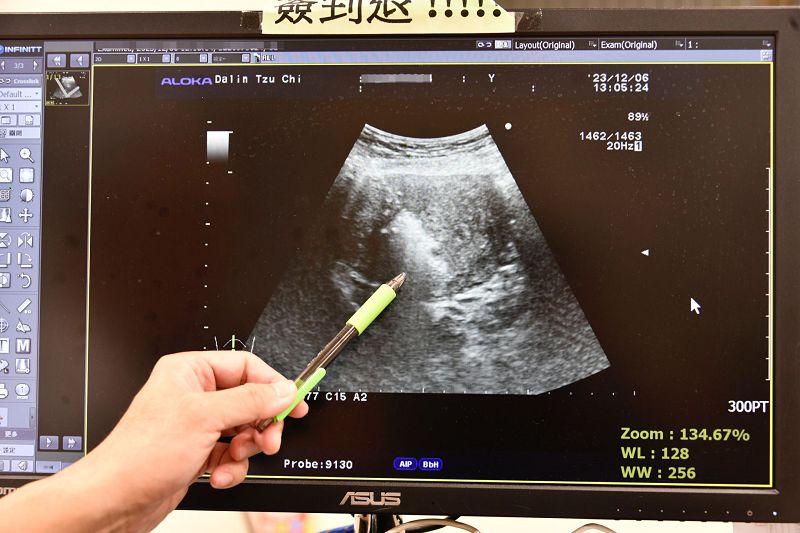

許鈞碩醫師指出,微波消融手術可透過腹部超音波導引,或腹腔鏡手術將微波消融針插入腫瘤,瞬間產生100度的熱能於腫瘤組織,搭配腹部超音波的影像協助定位,提供安全又快速的消融方式,不會有術後傷口疼痛或沾粘問題,本院至今已協助70例以上婦女解決痛經或經血量多等症狀,更提供患有子宮肌瘤或子宮肌腺瘤婦女,想保留生育功能或不想切除子宮多一項新選擇。微波消融是一種不用切開子宮且出血極少的創新治療方法,傷口小於0.2公分的針孔,不僅大幅度提高病患的生活品質,同時對身體的傷害也能降到最低,不僅術後恢復快,隔天即出院返家,一週後就能順利重回工作崗位。